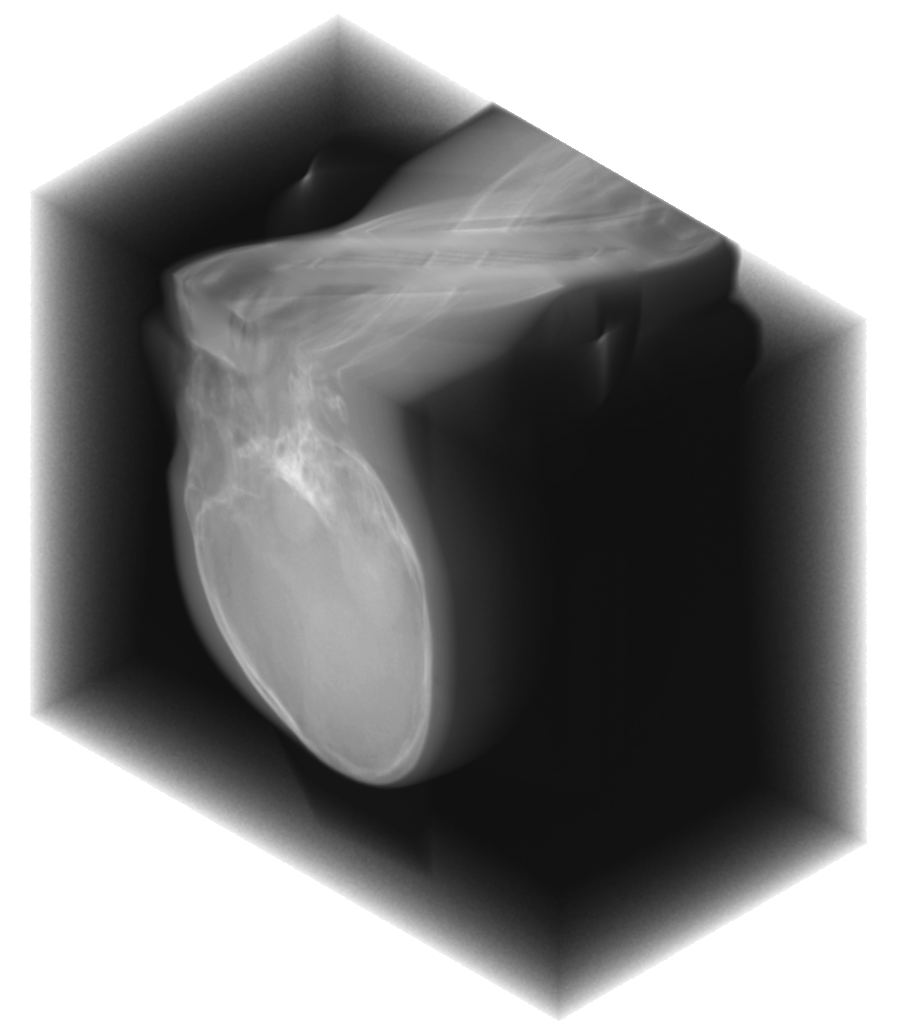

In practice, the complex wavelet transform is an effective tool for extracting singularities from a signal, as previously demonstrated for CT wavefront set extraction in [39]. In images and volumetric data, large-magnitude wavelet coefficients typically occur near jumps and edges. See Fig. 1 for an example of a sinogram containing two metal inserts, where the sum of the absolute values of the wavelet coefficients reveals the corresponding metal boundaries.

We propose a MAR method for projection-domain metal segmentation and inpainting, that uses 3D DT-CWT to find the edges of metals in the 3D sinogram. Fig. 2 shows the full workflow from 3D sinogram to metal artifact reduced reconstruction. The method is explained in detail below.

revealing the locations in the 3D sinogram space corresponding to the largest coefficients. See the 2nd row of Fig. 3 for an illustration of the resulting point cloud for two different 3D sinograms. Then, the result is binarized to by:

We computed the uncorrected FDK reconstruction, the image-domain hard-thresholding–based MAR reconstruction, and the proposed projection-domain complex wavelet MAR reconstruction for datasets (I–V). Fig. 4 shows selected slices from the reconstruction volumes for each dataset, displayed using identical windowing. The quantitative results of the metal segmentation are reported in Table 1 for datasets (I) and (II).

Dataset (II) presents a considerably more challenging MAR problem, featuring eight metal implants in a more complex anthropomorphic phantom. The uncorrected FDK reconstruction is again heavily affected by metal artifacts, which are prevalent in all slicing directions and obscure many anatomical structures. The HT-MAR method is able to reduce these artifacts to a reasonable extent, with projection inpainting restoring much of the missing information. However, the estimated metal boundaries are somewhat inaccurate and include portions of bright artifact regions. The CW-MAR method captures the metal boundaries more robustly. Nevertheless, some room for improvement remains, as projection inpainting introduces mild blurring in the vicinity of the metal regions.